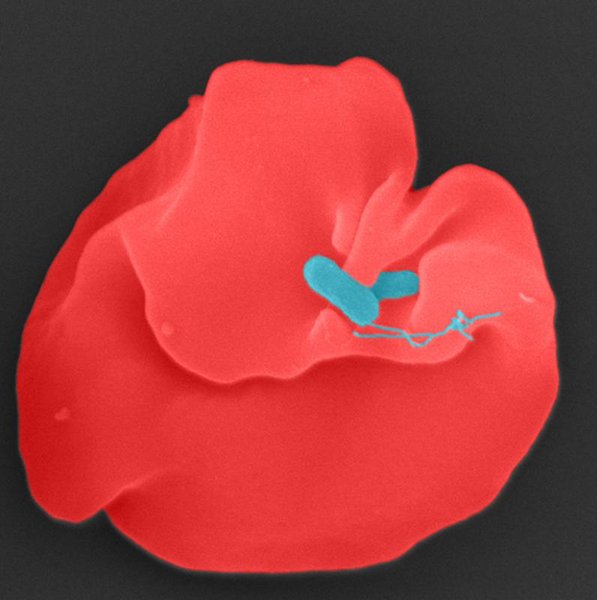

Das Oroya-Fieber ist zwar eine äußerst schwere Infektionskrankheit, gehört aber zu den so genannten vernachlässigten Tropenkrankheiten (Neglected Tropical Diseases). Denn die Infektion tritt – bisher – ausschließlich in hochgelegenen Tälern der südamerikanischen Anden auf, vor allem in Peru, aber auch in Ecuador und Kolumbien. Von der Forschung und der Arzneimittelentwicklung wurde die Krankheit daher bislang kaum beachtet. Ausgelöst wird das Oroya-Fieber durch das Bakterium Bartonella bacilliformis, das durch den Stich infizierter Sandmücken der Gattung Lutzomyia übertragen wird. Die Erkrankung beginnt meist mit hohem Fieber und einer massiven Zerstörung roter Blutkörperchen (Erythrozyten) und resultiert in einer sogenannten hämolytischen Anämie. Ohne antibiotische Behandlung endet das Oroya-Fieber in bis zu 90 Prozent der Fälle tödlich. Bereits 26 Prozent der Erreger sind resistent gegen das Standardantibiotikum Ciprofloxacin, was eine antibiotische Behandlung deutlich erschwert.

Ein internationales Forschungsteam um Prof. Volkhard Kempf von der Universitätsmedizin Frankfurt und der Goethe-Universität hat jetzt mehr als 1.700 genetische Varianten des Erregers hergestellt und analysiert und so zwei Proteine identifiziert, die Bartonella für die Zerstörung der roten Blutkörperchen benötigt: Ein sogenanntes Porin, das den Austausch zum Beispiel von Ionen mit der Umgebung ermöglicht, sowie ein Enzym namens α/β-Hydrolase, die beide zusammen für die Hämolyse verantwortlich sind. Strukturanalysen und gezielte Punktmutationen zeigten, dass die hämolytische Aktivität von Bartonella bacilliformis strikt von der enzymatischen Intaktheit der α/β-Hydrolase abhängt. „Beide Proteine sind im Zusammenspiel für die Zerstörung humaner Erythrozyten entscheidend und liefern damit eine Erklärung für das charakteristische Krankheitsbild des Oroya-Fiebers“, erklärt Dr. Alexander Dichter, Erstautor der Studie. „Das macht die α/β-Hydrolase zu einem geeigneten Zielprotein für medikamentöse Wirkstoffe.“